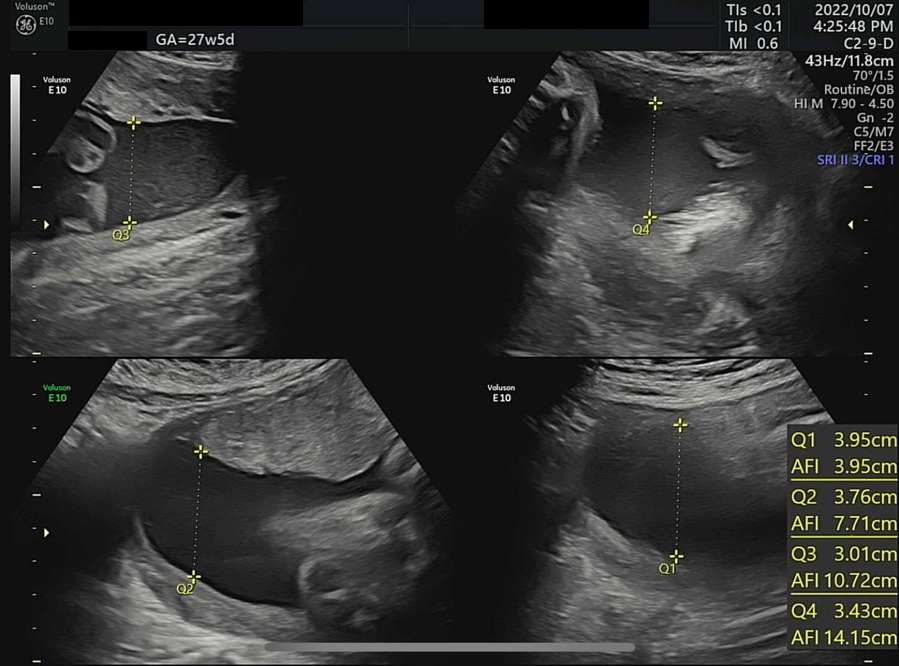

오늘은 병원에서 4D 입체 초음파를 찍기로 예약한 날이다. 입체 초음파는 아기의 모습을 입체적으로 사진 찍듯이 볼 수 있는데, 27주쯤에 찍어야 아기도 통통하게 살이 올라 예쁘게 찍힌다고 하여 이때 예약했다. 초음파실에 들어가서 아기가 주수에 맞게 잘 컸는지부터 확인했다. 2주 전 860g 정도였던 써니는 벌써 1kg를 돌파하여 1096g이 되었다. 임신 28주 이후에 체중이 1000g을 넘은 아기는 조산하여도 NICU(Neonatal Intensive Care Unit, 신생아 집중치료실)에서 치료를 받을 경우 생존 가능성이 95% 이상이다. 가장 친한 친구 중 한 명이 NICU 간호사인데, 매번 써니의 체중을 물어보았었다(직업병..?). 이제 1kg를 넘었으니 혹시나 세상에 일찍 나와도 이모한테 가면 살 수 있다. 그래도 이모 일터에는 가지 말자 써니야...

왼쪽부터 심박수, 양수량 확인, 머리 좌우 직경과 둘레 그리고 그에 따른 예상 분만일. ± 1주정도는 일반적이다.